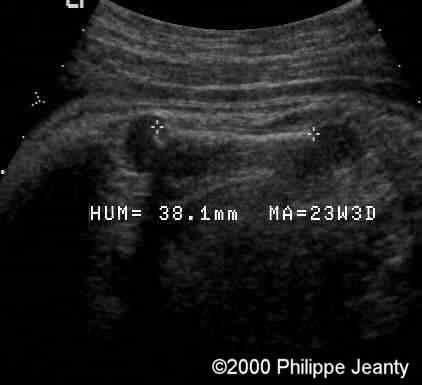

Humerus and femur (below) are too small (see chart below).

case0020-2

Femur

The femur (and humerus are way below the 5th percentile).